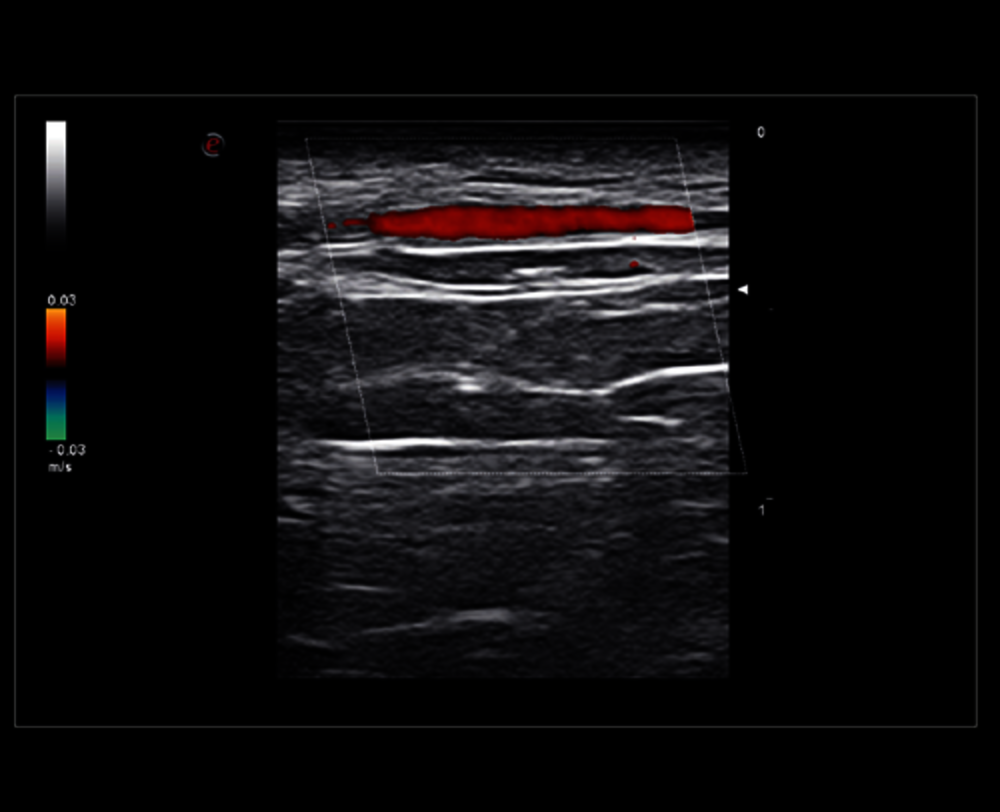

Vyšetření spánkové tepny pomocí sondy s velmi vysokou frekvencí (22 MHz)